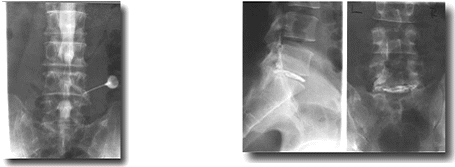

脊髄・椎間板・関節造影・神経根ブロック